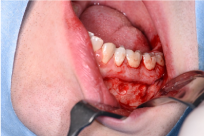

General clinical examinations displayed a rather short stature and frontal bossing. Intra-oral inspection revealed a poor general oral hygiene, with percussion pain at the lower left premolar (34) and second molar (37), but no pain sensation at the lower right second molar (47) (Figure 2a and 2b). Temperature and electric vitality tests elicited an adequate response at the lower right and left secondary molars (37-47). Radiographic examinations, including a panoramic view and cone beam CT-scan, showed periapical translucencies at the upper left central incisor, the lower left canine, the lower left primary and secondary molars and the lower right secondary molar (21-33-36-37-47) (Figure 2c). Moreover, it displayed enlarged pulp chambers and pulp horns, nearby the dentino-enamel junction.

Figure 2. Initial status of the patient. (a and b) Intraoral view of maxilla and mandible showing signs of dental crowding, but no apparent signs of caries. (c) Panoramic view from the first consultation.

Figure 3. Perioperative clinical photograph. Taken during the apical biopsy procedure in the lower left quadrant.